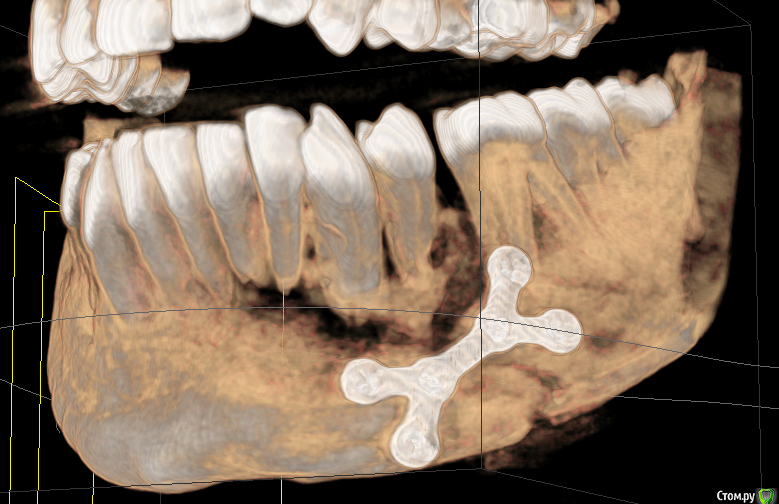

senchauser001 Опубликовано 17 октября, 2015 Поделиться Опубликовано 17 октября, 2015 Здравствуйте, уважаемые доктора. 2-го августа я получил одеосторонний перелом нижней челюсти со смещением, также был отломан альвеолярный отросток с 1-го по 5-ый зубы. Травма была очень серьезная. 3-го числа сделали операцию - остеосинтез титановой пластиной, наложилы шины, челюсти тягами не смыкали. Хирург попытался сохранить зубы и зафиксировал отломок одним шурупом плстины и шиной. Операцию делали из ротовой полости. Наружних повреждений в рузультате травмы я не получил.Через две недели сняли швы и только тогда я смог достаточно открыть рот чтобы разглядеть все полностью. В области 5го и 4го зубов наружней десны небыло, была видна кость и ушко титановой пластины. Врач удивился, сказал что пока на мне будут шины ничего не возможно сделать, а потом сделают небольшую пластику и все исправят. Назначил пасту солкосерил для регенерации тканей, мол поможет затянуться. Через 3 недели после операции сделали снимок и надели тяги для исправления прикуса. Картина на снимке врачю понравилась. 2 сентября сделали снимок и сняли тяги. Шины снимать не стали, т.к. зубы были подвижны, зашивать дисну также не стали. Велели продолжать мазать мазь, мол пусть сама затянется. 18-го сентября врачь решил зашить дисну, т.к. сама она не затагивалась. Через три дня рана раскрылась. Врач сказал что так не должно было быть, сказал придти через неделю, а пока продолжать мазать солкосерил. Через неделю, когда я пошел к врачю, тот сказал что в результате травмы нарушилось кровоснабжение и зашивать нет смысла, надо подождать. 2 октября наконецто сняли шины. Врачу очень не понравилось состояние зубов, они были подвижны, также он сказал что кость начала рассасываться. С наружней стороны дисна практически опустилась, видны были перегородки, кости еще больше оголились. Врачь направил меня к стоматологу, чтобы тот оценил какие зубы можно сохранить. Стоматологу состояние зубов не понравилась, сказал, что начался некроз кости и для адекватной оценки нужно сделать 3d томографию челюсти. Когда стоматолог рассмотрел томоргафию, то пришел в ужас и сказал что возможно придется удалять все 4 зуба, а также поврежденную кость. Я обратился в другую больницу на консультацию к члх, который осмотрев меня, и посмотрев томографию однозначно сказал, что нужно удалять весь отломок и отправил обратно к моему врачю. Я опять пошел к своему члх с этой томографией и только тогда, когда он ее посмотрел, то его осенило. Он сказал что отломанный альвеолярный отросток лишен кровоснабжения, он секвестируется, начелся некроз кости и его нужно удалять. Если бы не эта томография, он собирался удалить 2-ой и 4-ый зуб и натянуть все дисной. Все это время у меня не было не повышенной температуры, не болевых ощушений, ничего, что указывало бы на наличие восполительного процесса или чегото еще. В результате я потерял более чем 2 месяца безрезультатно. Сам члх достаточно опытный врачь, начальник отделения и кроме него меня смотрели другие члх из той же больницы. Если бы стоматолог не направил бы меня на 3d томаграфию, то не известно что было бы дальше. Теперь я не знаю как я могу доверять этому врачю, если он вовремя не обатил на это внимание и вел меня совсем другим путем? Каким образом после операции была оголена такая большая чась кости? Возможно ли было сохранить хотябы альвеолярный отросток удалением зубов? Как теперь можно будеть вставлять импланты? Стоит ли менять врача? Ваще мнение для меня очень важно. Заранее Спасибо! 1 Ссылка на комментарий

senchauser001 Опубликовано 20 октября, 2015 Автор Поделиться Опубликовано 20 октября, 2015 Сегодня сделалаи секвестрэктомию, удалили весь секвестр. Скажите пожалуста, нужно ли снимать имплант (пластину) и через скодько времени? Ссылка на комментарий